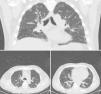

Laboratory tests showed that he had normocytic normochromic anemia. Rheumatoid factor was 65.3IU/L, C-reactive protein 290.4mg/L, total creatine kinase 3.6U/L, creatinine 2.8mg/dL, urea 86.5mg/dL and blood urea nitrogen 40mg/dL. In urine, we observed proteinuria with a level of 75mg/dL and erythrocytes at 260cells/mL, with active sediment characterized by dysmorphic erythrocytes. No evidence of bacteria in urine culture, blood culture, sputum culture or stool culture. The results of a viral panel for hepatitis C virus, hepatitis B virus and human immunodeficiency virus were negative. High-resolution computed tomography of the chest revealed interstitial involvement with a pattern of irregular septal thickening and areas of alveolar filling with air bronchogram in peripherally distributed patches (pattern of organizing pneumonia) (Fig. 1). An electromyographic study showed a pattern indicating a demyelinating disease. Bronchoalveolar lavage demonstrated nonspecific chronic and acute inflammation. Studies focusing on autoimmunity found the patient to be positive for antinuclear antibodies at a titer of 1:320 with a mitochondrial pattern, as well as for perinuclear antineutrophil cytoplasmic antibodies (p-ANCA). The specificity of anti-myeloperoxidase antibodies (anti-MPO) was positive; whereas that of other autoantibodies (anti-Jo-1, anti-Scl-70, anti-double-stranded DNA and anti-cyclic citrullinated peptide antibodies) was negative. The histopathological study of the lung specimen demonstrated small-vessel vasculitis with extensive areas of fibrosis and pulmonary emphysema (Fig. 2).